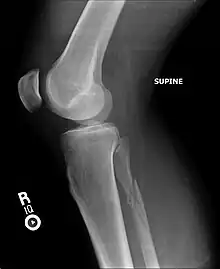

Segond fracturePaul Segondlateral tibial plateau avulsion fracture with anterior cruciate ligament tearSegond fracture at Who Named It?

Bumper fractureCar bumpercompression fracture of lateral tibial plateauforced valgus of knee when struck from side by car bumperBumper fracture Archived 2022-01-21 at the Wayback Machine at TheFreeDictionary.com